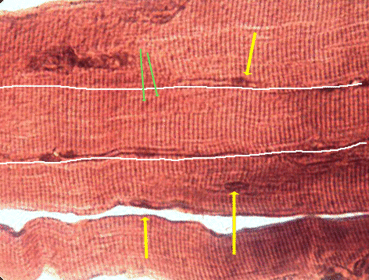

A. Name B. Location C. Voluntary or Involuntary? D. Multi or uninucleate? A. Skeletal Muscle B. Around bone C. Voluntary D. Multinucleate

A. Name of specific tissue type B. Location of tissue C. Name of structure separating individual cells D. Name of two types of junctions in the above structure E. Voluntary of involuntary? F. Multi or uninucleate? A. Cardiac Muscle B. Heart C. Intercalated discs D. Gap junction and desmosomes E. Involuntary F. Uninucleate

look at differences